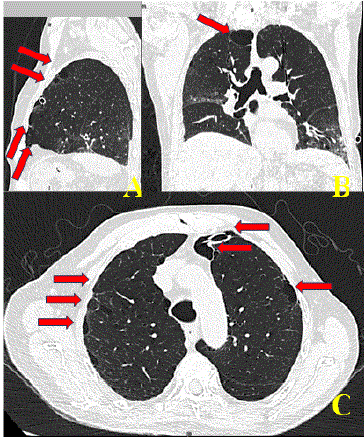

Image D: Simple chest CT study in longitudinal (A), coronal (B) and axial (C) sections where the proper placement of the endopleural tube that resolved the respiratory problem due to pneumothorax is observed and where multiple well-defined hypodense images are observed within the pulmonary parenchyma that corresponds to the bullous disease of small elements (arrows).